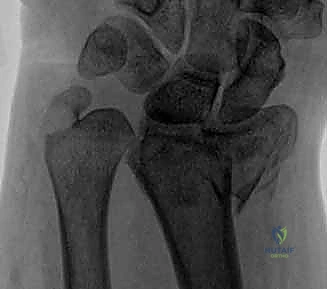

1. كسور الناتئ الإبري للزند (Ulnar Styloid Fractures)

الناتئ الإبري هو البروز العظمي الذي يمكنك الشعور به في الجزء الخارجي من معصمك.

* كسور قمة الناتئ الإبري (Tip Fractures): غالبًا ما تكون كسورًا قلعية (Avulsion fractures) صغيرة. عادة ما تكون مستقرة ولا تؤثر بشكل كبير على المفصل (DRUJ).

* كسور قاعدة الناتئ الإبري (Base Fractures): هي الأخطر. نظرًا لأن الأربطة الرئيسية للـ TFCC تتصل بقاعدة الناتئ، فإن الكسر هنا يعني غالبًا فقدان استقرار المعصم. يتطلب هذا النوع تقييمًا دقيقًا جدًا لمدى ثبات المفصل بعد تثبيت كسر الكعبرة (إن وجد).

- المفصل الزندي الكعبري البعيد (DRUJ): هو المفصل الذي يربط بين نهايات الكعبرة والزند عند المعصم. يدور عظم الكعبرة حول رأس الزند من خلال هذا المفصل أثناء حركات الكب (تدوير الساعد بحيث يكون باطن اليد لأسفل) والبسط (تدوير الساعد بحيث يكون باطن اليد لأعلى). استقرار هذا المفصل لا يعتمد فقط على العظام، بل يعتمد بشكل كبير على التوافق العظمي بين رأس الزند والثلمة الكعبرية (الشق السيني - Sigmoid Notch) في الكعبرة.

المركب الغضروفي الليفي الثلاثي (TFCC) وأهميته القصوى

يُعد المركب الغضروفي الليفي الثلاثي (Triangular Fibrocartilage Complex - TFCC) بمثابة "غضروف الركبة" بالنسبة للمعصم. إنه هيكل معقد يتكون من أربطة وغضاريف تربط المفصل الزندي الكعبري البعيد بعظام الرسغ.

* وظيفة الـ TFCC: يوفر استقرارًا حيويًا للمفصل (DRUJ)، ويساعد في امتصاص الصدمات وتوزيع الأحمال الميكانيكية عبر المعصم أثناء رفع الأشياء الثقيلة أو الاستناد على اليد.

* الارتباط بالناتئ الإبري: ترتبط العديد من أربطة الـ TFCC مباشرة بالناتئ الإبري للزند (Ulnar Styloid). لذلك، فإن أي كسر في قاعدة الناتئ الإبري غالبًا ما يصاحبه تمزق في هذا المركب الغضروفي، مما يؤدي إلى عدم استقرار شديد في المعصم يستوجب تدخلًا جراحيًا دقيقًا، وهو ما يبرع فيه الأستاذ الدكتور محمد هطيف باستخدام تقنيات المناظير (Arthroscopy).

- علامة مفتاح البيانو (Piano Key Sign): وهي علامة سريرية هامة تدل على تمزق أربطة المفصل الزندي الكعبري البعيد (DRUJ). عند الضغط على رأس الزند البارز، فإنه ينزل لأسفل، وبمجرد إزالة الضغط، يرتد لأعلى مثل مفتاح البيانو.

1. الأشعة السينية (X-rays): بوضعيات متعددة (أمامية خلفية، وجانبية دقيقة). الوضعية الجانبية الحقيقية (True Lateral) حاسمة لاكتشاف أي خلع جزئي في المفصل (DRUJ).

2. الأشعة المقطعية ثلاثية الأبعاد (3D CT Scan): تُستخدم في الكسور المفتتة أو كسور رأس الزند المفصلية المعقدة، حيث تعطي خريطة دقيقة للجراح قبل الدخول لغرفة العمليات.

3. الرنين المغناطيسي (MRI): يُطلب عند الاشتباه القوي بوجود تمزقات في الأربطة والمركب الغضروفي (TFCC) التي لا تظهر في الأشعة السينية.